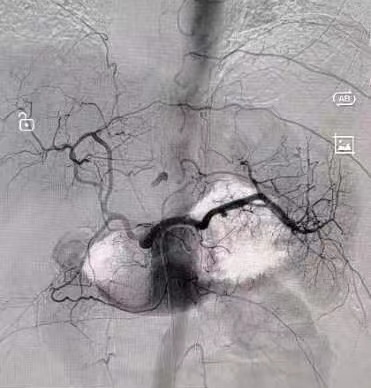

在春节期间,急性腹痛、急性心肌梗死、呼吸衰竭、脑卒中、各种创伤、发热等各类突发性疾病是急诊接诊的主要人群。大年三十,急诊来了一位腹痛患者,接诊医师迅速对患者的病情进行全方位了解,影像学检查报:膈下游离气体,符合消化道穿孔表现,迅速联系急诊外科组医生,协调手术室行剖腹探查手术,术中发现胃底部一处约1cm大小穿孔,周围大量脓液,程三放教授与党旭升医师迅速进行手术修补处理,手术顺利,术后安全返回病房,患者目前恢复良好,近期可以出院。大年初四,一位肝癌破裂出血患者急诊就诊,来院时腹腔大量积血,出现了出血性休克等表现,急需快速止血,我科介入组医师迅速为患者进行了腹腔干动脉、肝动脉造影,发现“犯罪血管”,行肝左动脉栓塞术,稳定了生命体征,考虑患者为肿瘤破裂出血,即使介入栓塞仍有再出血可能,随后我科外科组医师行进一步剖腹手术治疗创造了条件,术程顺利,术后转入急诊ICU病房监护,现患者已脱离生命危险,介入与外科手术的配合,为患者创造最大收益,体现了我科各组间流畅的配合协作,与时间赛跑,为生命健康保驾护航。

急诊介入组医师在行腹腔干动脉、肝动脉造影、肝左动脉栓塞手术

肝癌破裂出血介入术前